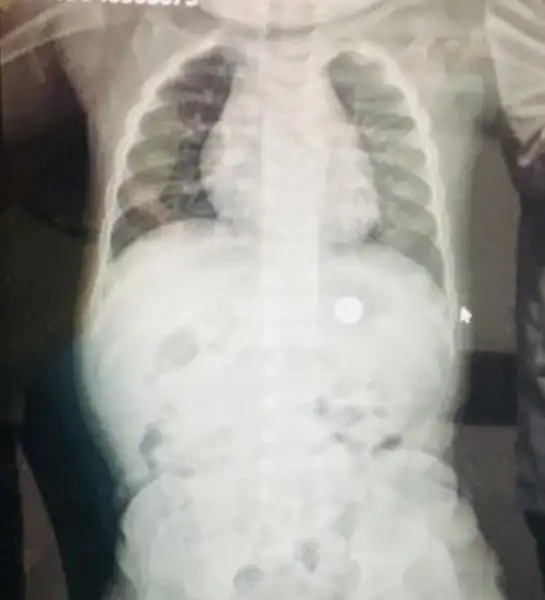

Kızlar oğlum pil yuttu. Akşamdan beri çevre ildeki tıp fak geldik. Büyük kızla ikizini bakıcıya bıraktım. Saat 11 gibi endoskopi ile çıkardılar. Hala şoku atlatamadım :KK43:. Dua edin sabah çıkalım :KK43:( hep benim hatam :KK43: